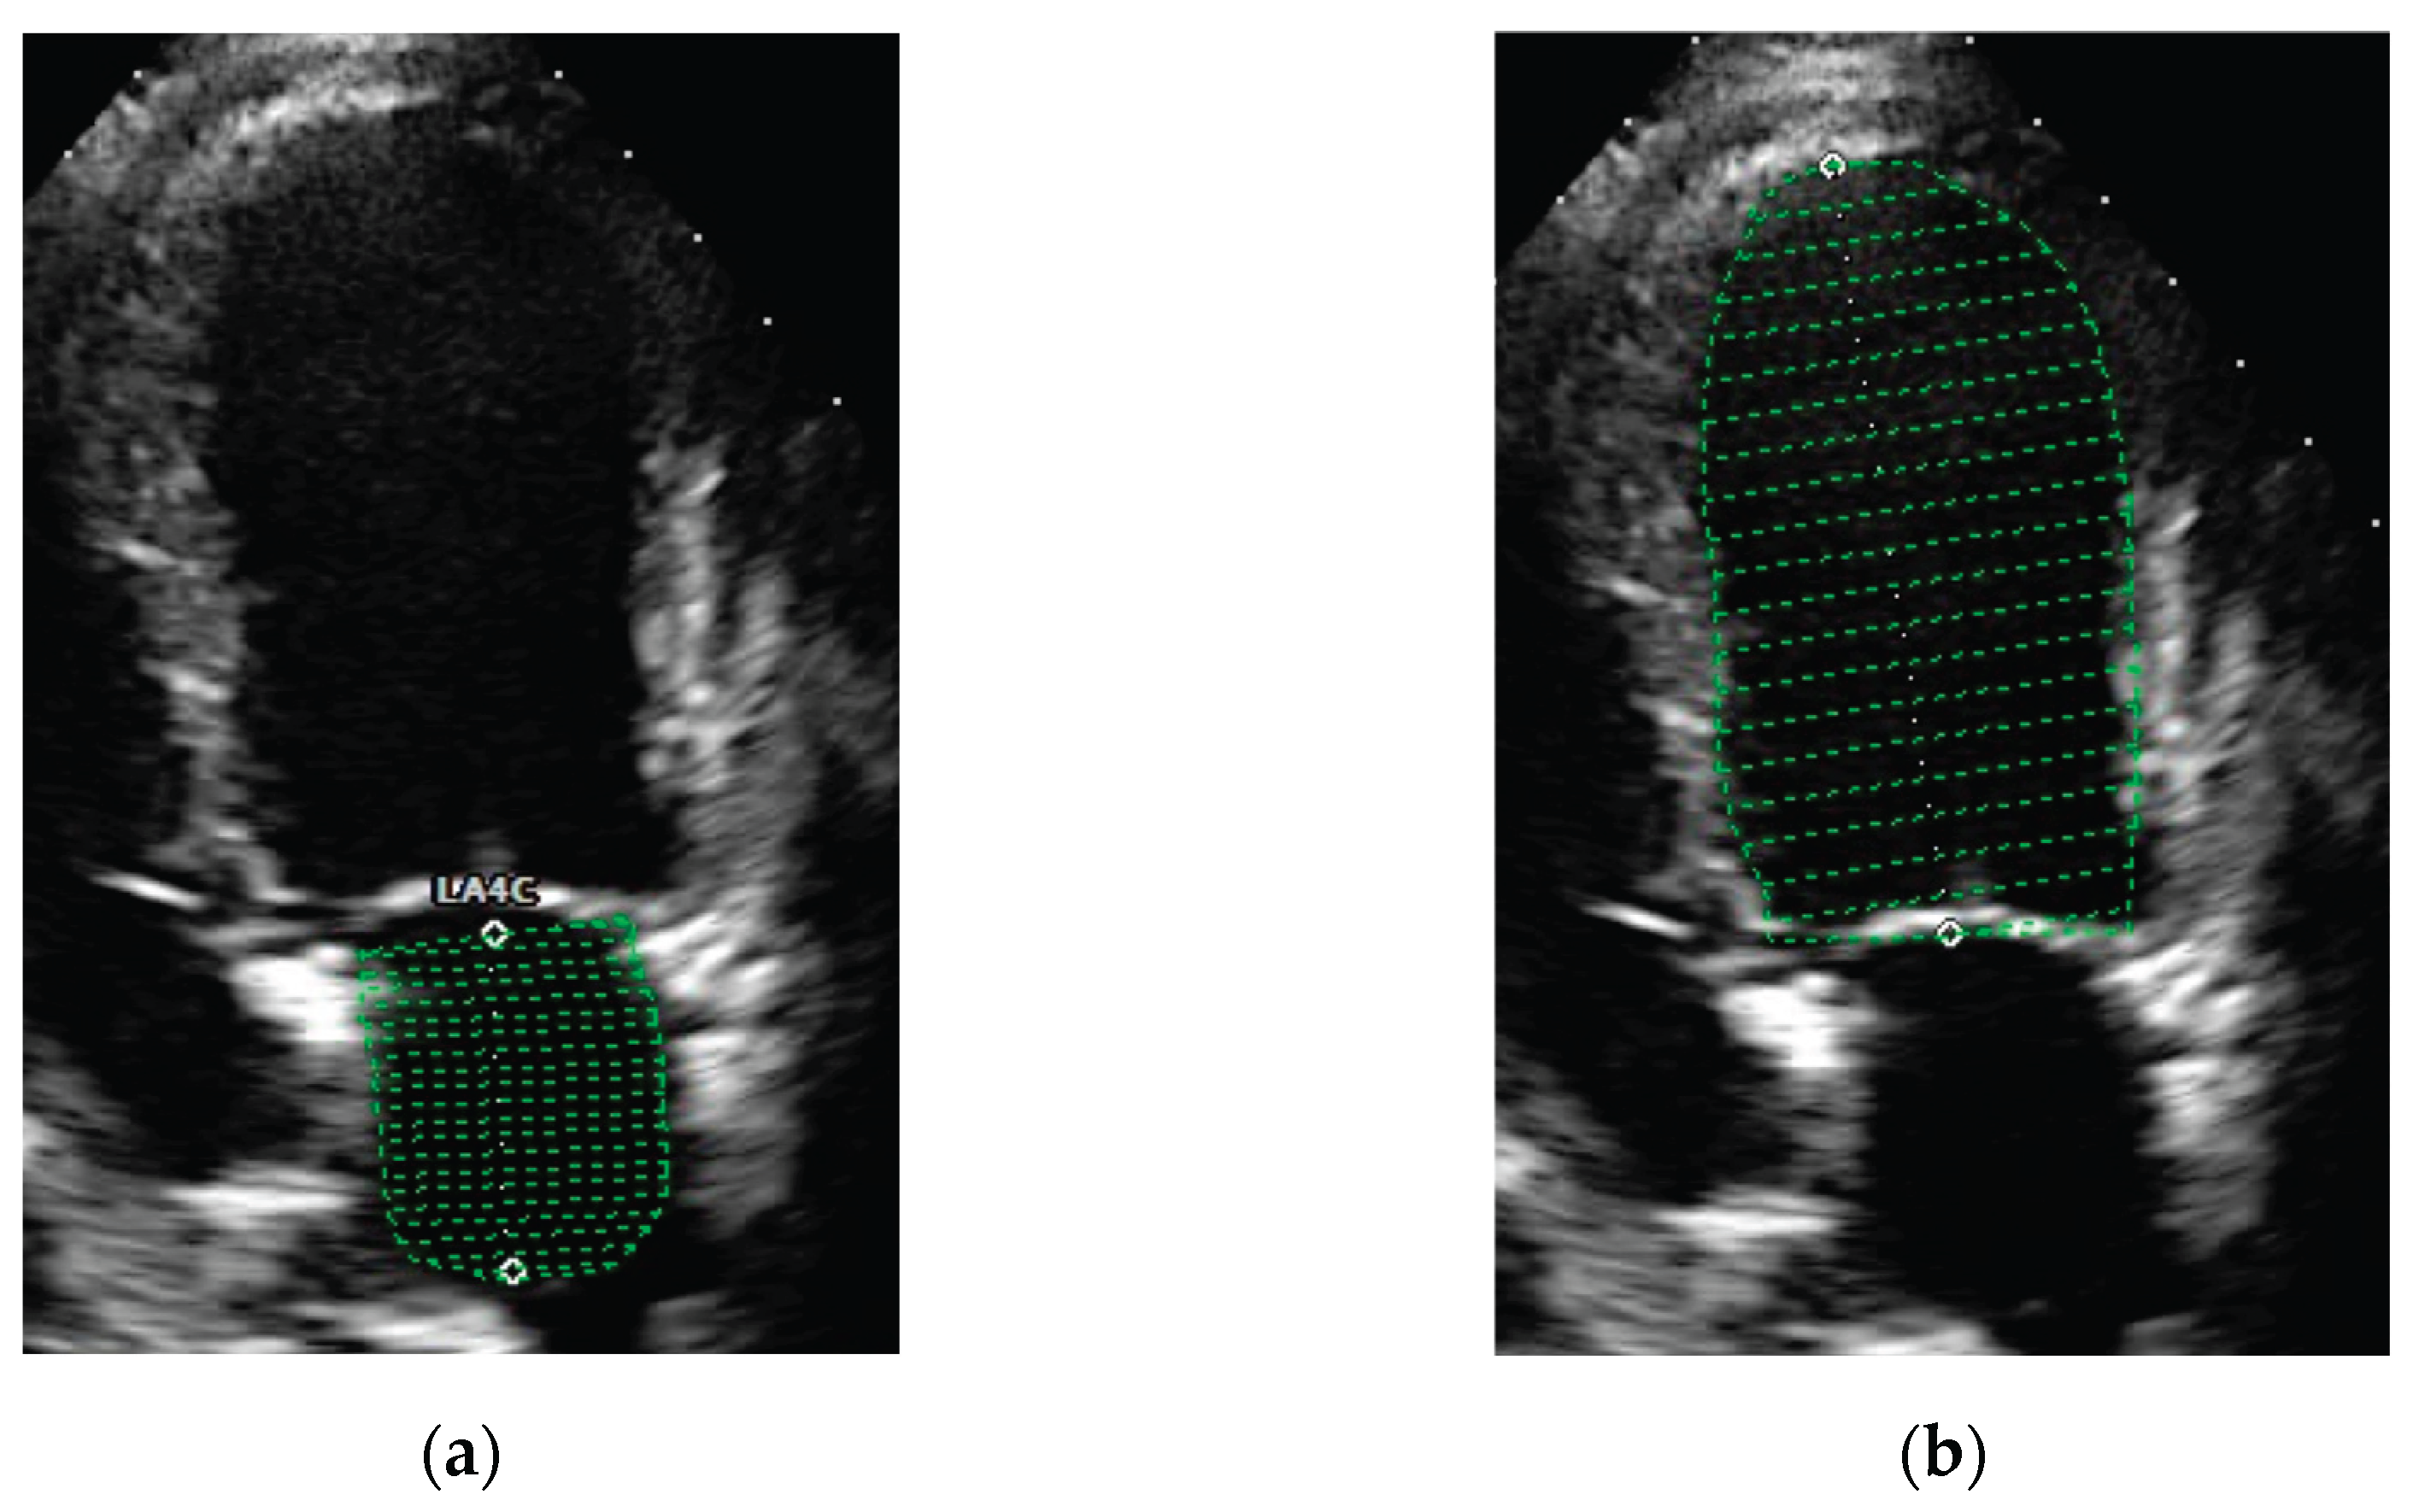

The same investigator (FV) selected appropriate frames from stored cineloops of each dog and performed the measurements from those frames. LA and LV volumes were measured at the same end-diastolic phase defined by the frame just after mitral valve closure (around the onset of the QRS complex) and at the same end systolic phase defined by the frame just before mitral valve opening (typical after end of the T wave). Echocardiographic volumes were measured using a single plane Simpson’s Method of Discs from the apical four-chamber view. The internal border of the LA was traced manually beginning at the septal mitral annulus (first hinge point), around the LA roof and ending at the lateral mitral annulus (second hinge point) using the blood-tissue interface (Figure 1). The ostia of the pulmonary veins were excluded, and a straight line drawn from hinge point to hinge point across the mitral valve annulus defined the boundary of LA. The height of the stacked discs was selected to be perpendicular to the midpoint of the mitral valve annulus, bisecting LA. The internal border of the LV was traced manually beginning at the septal mitral annulus, around the apex and ending at the lateral mitral annulus, using the blood-tissue interface (Figure 1). These two points were joined by a bisecting line by software on the ultrasound systems. The maximum length of the LV was defined by the distance between the mitral annulus and the apex.

Figure 1. Representative echocardiographic images of view and method of obtaining left atrial and left ventricle volumes estimates using Simpson’s Method of Discs (green lines). Left atrial (a) and left ventricle (b) volumes estimates obtained from left apical four-chamber view at end-diastole.